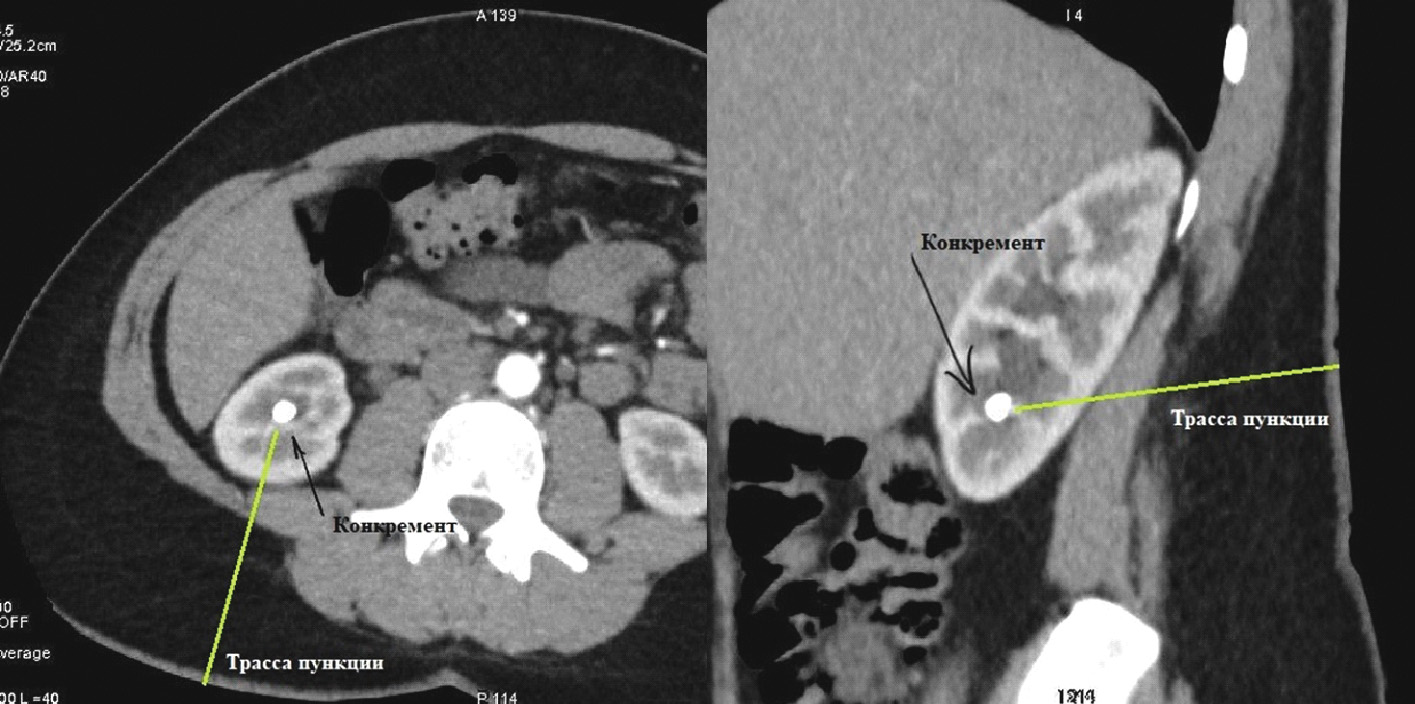

Нами были изучены результаты 60 мини-перкутанных литотрипсий. Все они проводились с использованием 3D-планирования доступа в программах «Автоплан», «Луч-С» и VessellQ Xpress. При нативном и отсроченном сканировании находили целевую группу чашечек, содержащую конкремент. В артериальную фазу определяли тип кровоснабжения почки и ее малососудистые зоны (рисунки 1, 2).

Рисунок 1. Определение строения артериального русла почки (артерии выделены дополнительно).

После определения линейных размеров и сосудистой анатомии почки с выявлением малососудистых зон осуществлялось планирование точки и траектории доступа с нанесением на кожу визуальных маркеров для последующей интраоперационной оценки точки пункции и направления движения пункционной иглы (рисунок 3).

Рисунок 3. Планирование трассы чрескожного доступа.